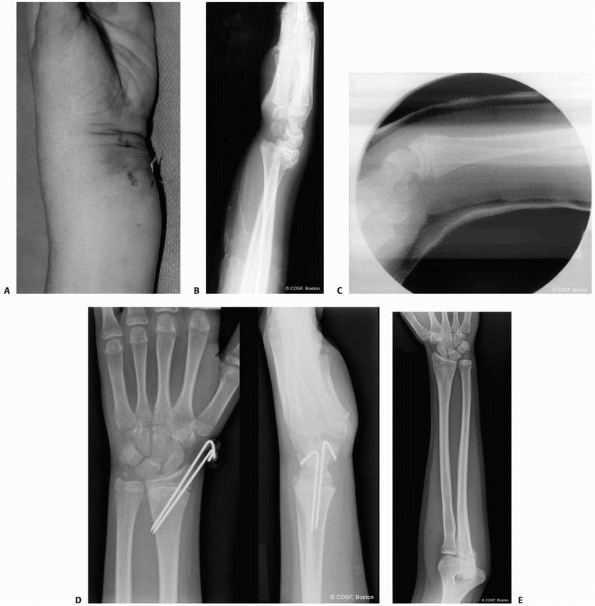

radial physeal fractures are still controversial. The best indication

is a displaced radial physeal fracture with median neuropathy and

significant volar soft tissue swelling (Fig. 9-17).239

These patients are at risk for development of an acute carpal tunnel

syndrome or forearm compartment syndrome with closed reduction and

well-molded cast immobilization.34,91,195,239

The torn periosteum volarly allows the fracture bleeding to dissect

into the volar forearm compartments and carpal tunnel. If a tight cast

is applied with a volar mold over that area, compartment pressures can

increase dangerously. Percutaneous pin fixation allows the application

of a loose dressing, splint, or cast without the risk of loss of

fracture reduction.

![]() |

|

FIGURE 9-17 A.

Clinical photograph of patient with a displaced Salter-Harris type II fracture of the distal radius. The patient has marked swelling volarly with hematoma and fracture displacement. The patient had a median neuropathy upon presentation. B. Lateral radiograph of the displaced fracture. C. Lateral radiograph following closed reduction and cast application. Excessive flexion has been utilized to maintain fracture reduction, resulting in persistent median neuropathy and increasing pain. D. Radiographs following urgent closed reduction and percutaneous pinning. E. Follow-up radiograph depicting distal radial physeal arrest and increased ulnar variance. |